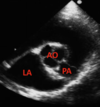

Long-axis left ventricular outflow view.

Identify the structure indicated by the number 2

right atrium